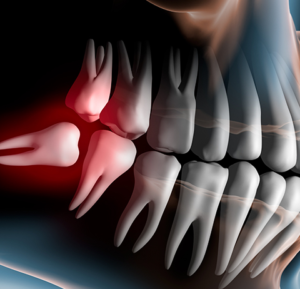

- Khám và tư vấn: Kiểm tra tổng quát tình trạng răng miệng, tiến hành chụp CT Scan. Phân tích, đánh giá cấu trúc xương cũng như độ dày của xương, lên kế hoạch chi tiết điều trị cho bệnh nhân

Tiến trình cắm implant có thể kèm theo trường hợp ghép xương, tùy vào cơ địa từng bệnh nhân mà Nha Sĩ sẽ đưa ra kế hoạch chi tiết trước khi tiến hành cắm ghép.